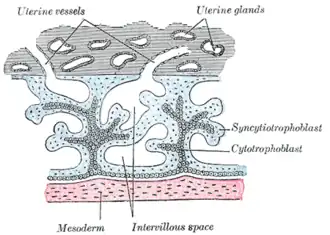

The trophoblast will also develop two sub-layers: the cytotrophoblast, which is in front of the syncytiotrophoblast, which in turn lies within the endometrium.[10] Next, another layer called the exocoelomic membrane or Heuser's membrane will appear and surround the cytotrophoblast, as well as the primitive yolk sac.[11] The syncytiotrophoblast will grow and will enter a phase called lacunar stage, in which some vacuoles will appear and be filled by blood in the following days.[10][11] The development of the yolk sac starts with the hypoblastic flat cells that form the exocoelomic membrane, which will coat the inner part of the cytotrophoblast to form the primitive yolk sac. An erosion of the endothelial lining of the maternal capillaries by the syncytiotrophoblastic cells results in the formation of the maternal sinusoids from where the blood will begin to penetrate and flow into and through the trophoblastic lacunae to give rise to the uteroplacental circulation.[12][13] Subsequently, new cells derived from yolk sac will be established between trophoblast and exocoelomic membrane and will give rise to extra-embryonic mesoderm, which will form the chorionic cavity.[11]

At the end of the second week of development, some cells of the trophoblast penetrate and form rounded columns into the syncytiotrophoblast. These columns are known as primary villi. At the same time, other migrating cells form into the exocoelomic cavity a new cavity named the secondary or definitive yolk sac, smaller than the primitive yolk sac.[11][12]

After ovulation, the endometrial lining becomes transformed into a secretory lining in preparation of accepting the embryo. It becomes thickened, with its secretory glands becoming elongated, and is increasingly vascular. This lining of the uterine cavity (or womb) is now known as the decidua, and it produces a great number of large decidual cells in its increased interglandular tissue. The blastomeres in the blastocyst are arranged into an outer layer called the trophoblast. The trophoblast then differentiates into an inner layer, the cytotrophoblast, and an outer layer, the syncytiotrophoblast. The cytotrophoblast contains cuboidal epithelial cells and is the source of dividing cells, and the syncytiotrophoblast is a syncytial layer without cell boundaries.

The syncytiotrophoblast implants the blastocyst in the decidual epithelium by projections of chorionic villi, forming the embryonic part of the placenta. The placenta develops once the blastocyst is implanted, connecting the embryo to the uterine wall. The decidua here is termed the decidua basalis; it lies between the blastocyst and the myometrium and forms the maternal part of the placenta. The implantation is assisted by hydrolytic enzymes that erode the epithelium. The syncytiotrophoblast also produces human chorionic gonadotropin, a hormone that stimulates the release of progesterone from the corpus luteum. Progesterone enriches the uterus with a thick lining of blood vessels and capillaries so that it can oxygenate and sustain the developing embryo. The uterus liberates sugar from stored glycogen from its cells to nourish the embryo.[14] The villi begin to branch and contain blood vessels of the embryo. Other villi, called terminal or free villi, exchange nutrients. The embryo is joined to the trophoblastic shell by a narrow connecting stalk that develops into the umbilical cord to attach the placenta to the embryo.[11][15] Arteries in the decidua are remodelled to increase the maternal blood flow into the intervillous spaces of the placenta, allowing gas exchange and the transfer of nutrients to the embryo. Waste products from the embryo will diffuse across the placenta.